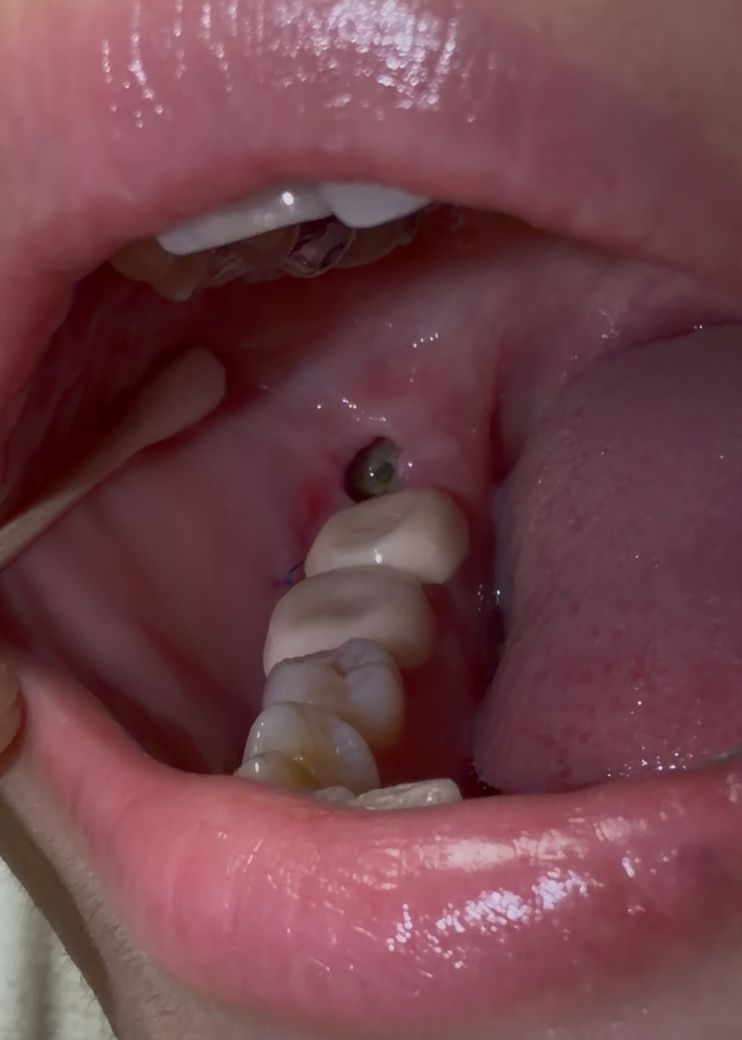

사랑니 발치후 4일차입니다. 뭔가 이상한게 보여요

흰색이 차오르는 듯 하다 가운데 은색, 녹색? 빛이 나는게 갑자기 보이기 시작하는데 뭘까요..?

염증 냄새도 계속 느껴져요

• 1번 째 사진